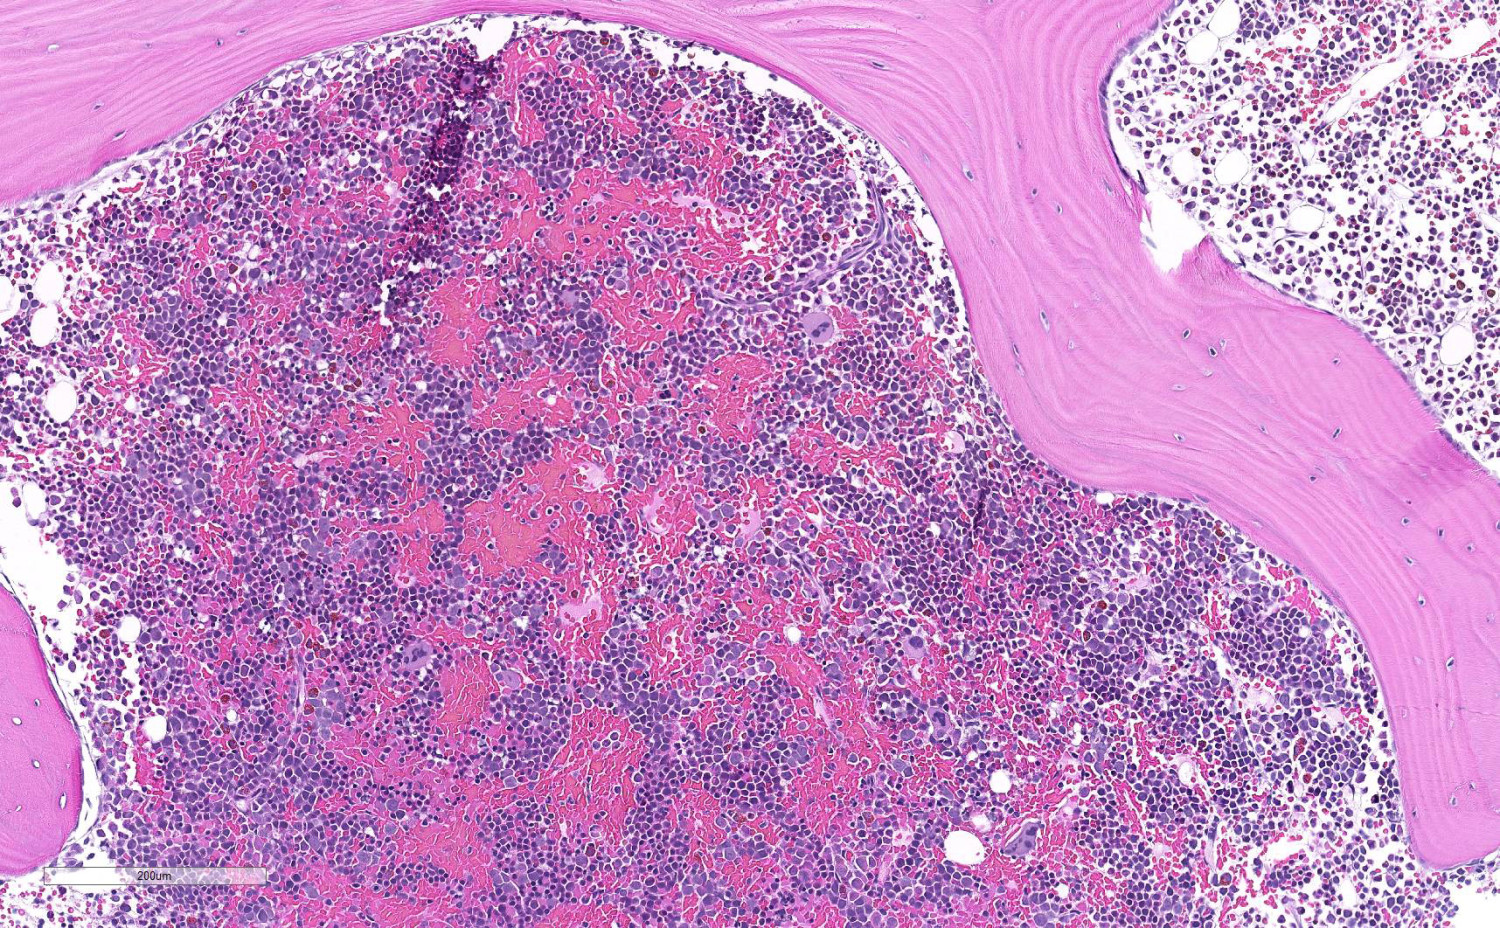

Det finnes ingen enkel test for å stille diagnosen (6). I praksis vil den først bli aktuell etter at man har tatt en benmargsbiopsi. Sammenlignet med normal benmarg (figur 1) vil man ved aplastisk anemi finne uttalt hypoplasi av hematopoese, og margrom domineres av fettceller (figur 2). I biopsien kan man samtidig vurdere om det foreligger annen primær malign benmargssykdom, lymfoproliferativ sykdom, metastaser, inflammatoriske eller infeksiøse prosesser eller tilstand med økt produksjon av blod, som ved hemolytisk anemi (figur 3).